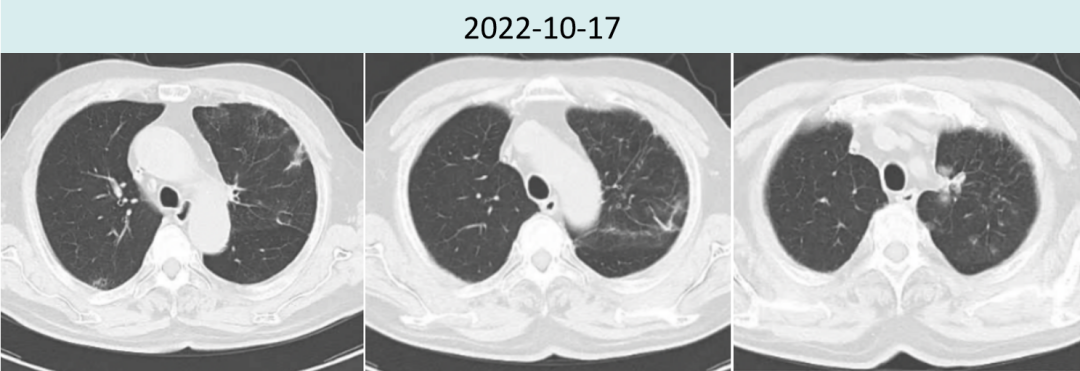

2022年10月17日斯鲁利单抗联合安罗替尼治疗六周期后,胸部CT提示肿瘤病灶较前继续缩小,疗效评价持续PR(2.9cm→1.4cm)。

图3.患者治疗前后胸部病灶及肺炎情况对比

在应用斯鲁利单抗伊始,CT显示该患者间质性肺炎仍未完全消退,使用斯鲁利单抗治疗期间未出现间质性肺炎加重或其他免疫不良反应。目前患者已应用斯鲁利单抗联合安罗替尼治疗6周期,持续PR大于4月。我们将继续跟进患者疗效与不良反应发生情况,期待为患者带来长久生存获益。